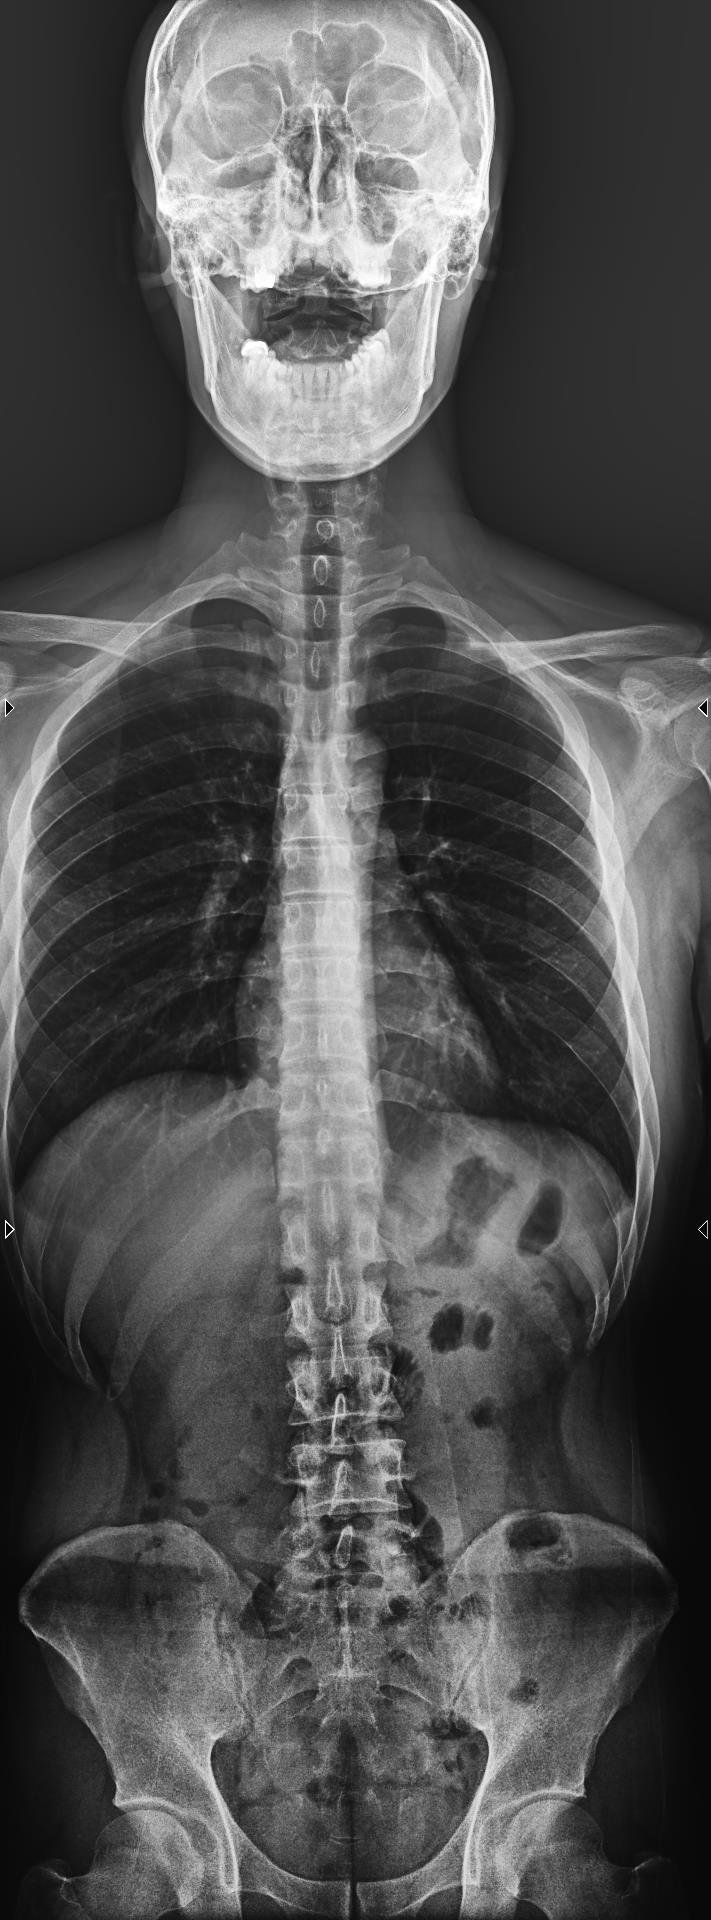

Chụp X-quang cột sống là kỹ thuật sử dụng tia X để ghi lại hình ảnh cấu trúc xương của cột sống, bao gồm các đốt sống cổ, ngực, thắt lưng và xương cùng. Với X-quang cột sống toàn phần, bác sĩ có thể quan sát cột sống như một chỉnh thể thống nhất, thay vì chỉ nhìn từng đoạn riêng lẻ.

Chụp X-quang toàn bộ cột sống là phương pháp chẩn đoán hình ảnh giúp bác sĩ đánh giá tổng thể cấu trúc xương sống, từ đó phát hiện sớm nhiều bất thường và bệnh lý quan trọng. Thay vì chỉ quan sát từng đoạn riêng lẻ, kỹ thuật này cho phép nhìn cột sống như một chỉnh thể thống nhất, phản ánh đúng trục chịu lực và sự liên kết giữa các vùng cổ – ngực – thắt lưng – xương cùng.

Hình ảnh X-quang toàn bộ cột sống được ghi nhận ở nhiều tư thế, nhiều góc độ, giúp bác sĩ:

Có cái nhìn tổng thể về cấu trúc xương, đĩa đệm, dây chằng.

Đánh giá trục chịu lực và sự cân bằng của cột sống.

Đưa ra chẩn đoán chính xác và lựa chọn phác đồ điều trị phù hợp.